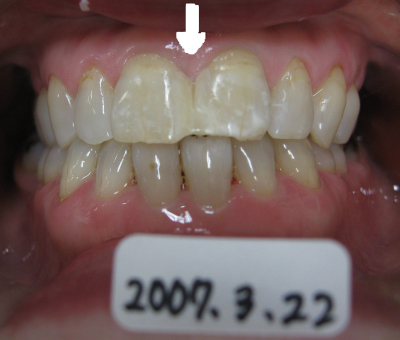

歯と歯の間にプラスチックを流し込んで約10分で治療終了。

歯は一切削っていません。

2012年08月11日現在、変色もなく良好。